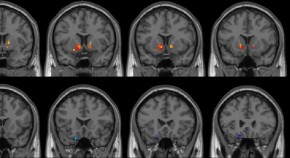

Pathogen triggered N-terminal degradation of NLRP1 and CARD8 by the proteasome releases their C-terminal UPA-CARD fragments (CT) to form the inflammasome, which in turn activates caspase-1. Here, the authors present the cryo-EM structures of the NLRP1-CT and CARD8-CT helical filaments as well as the ASC−caspase-1 octamer structure, which together with in vitro and cell based assays provide further insights into the architecture and specificity of the active NLRP1 and CARD8 inflammasomes.